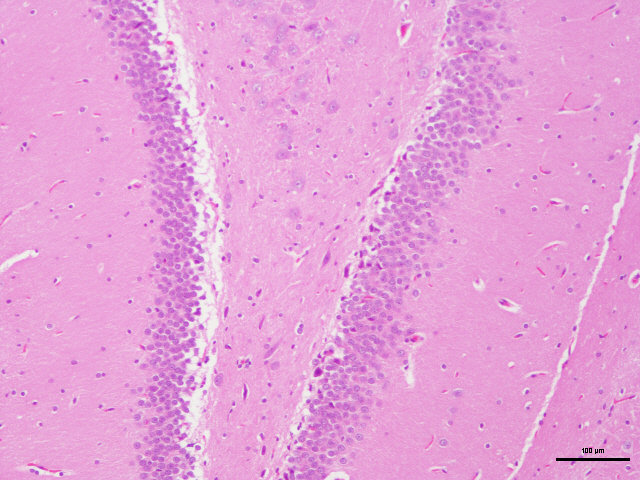

样片参考:

脑